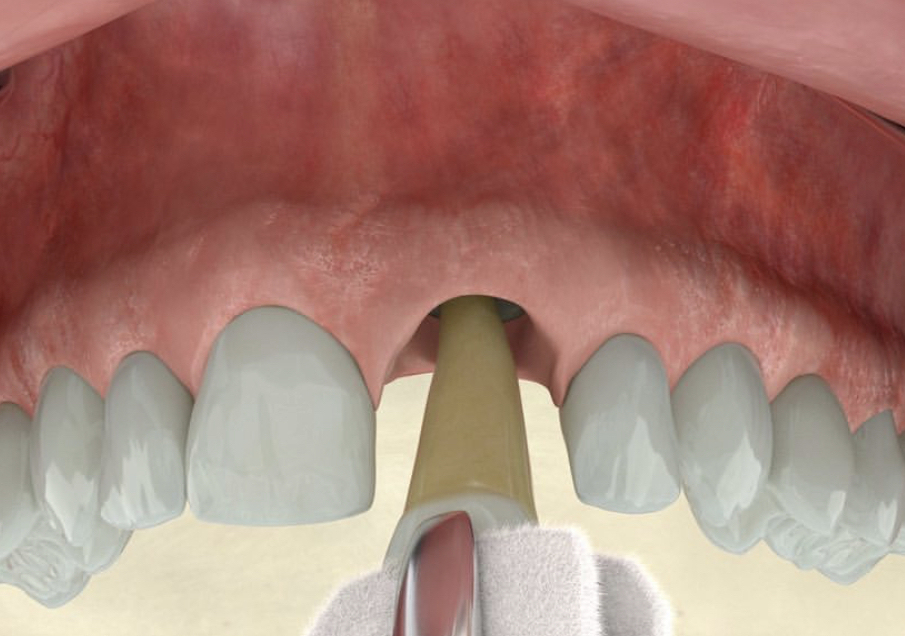

Este curso ofrece las bases biológicas para entender el porqué de la mucositis y comprender por qué 1 paciente con implante de cada 4 desarrolla Periimplantitis.Incluye los factores de riesgo y como tratarlos de forma predictiva en el tiempo.